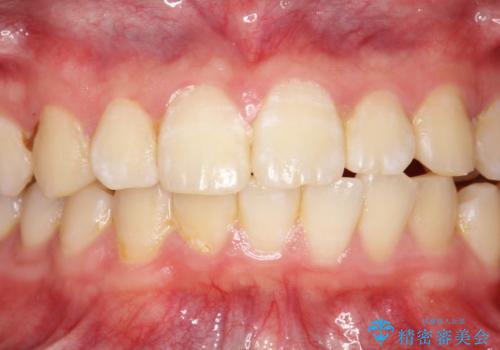

- 10年ぶりに歯科医院に来院された方です。クリーニングは人生で初めてとのことでした。

全体的に着色と汚れの量が多いため、PMTC60分コースで行いました。